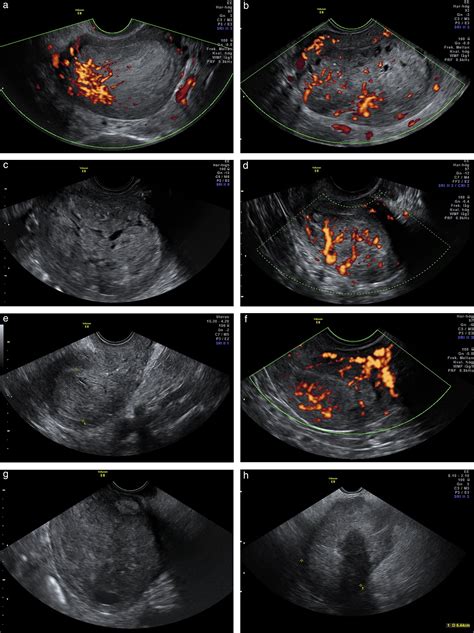

There are two primary types of ultrasound used to examine the endometrium: transabdominal and transvaginal. For the best visualization of the uterus, the transvaginal approach is generally preferred.

• Transvaginal Ultrasound: A specialized, slim transducer is inserted into the vagina. This provides much higher resolution images, particularly of the endometrium, because the transducer is positioned closer to the uterus.

In many cases, a doctor may suggest a saline infusion sonohysterography (SIS). During this procedure, sterile saline is gently injected into the uterine cavity through a thin catheter. This fluid expands the uterine cavity, allowing the ultrasound to highlight potential polyps, fibroids, or thickened areas of the lining that might be missed on a standard scan.

While an Endometrial Cancer Ultrasound is highly effective, it has limitations that patients and providers must understand. Firstly, it is a morphological assessment; it looks at structure, not cellular function. Therefore, it cannot differentiate between benign hyperplasia (an overgrowth of cells), polyps, or malignant cells.

Secondly, visualization can be impaired in certain patients. Factors such as uterine position (e.g., a retroverted uterus), obesity, or large fibroids can make it challenging to obtain a clear, accurate measurement of the endometrial stripe. In these instances, the physician may recommend alternative imaging, such as magnetic resonance imaging (MRI), or proceed directly to an endometrial biopsy to ensure an accurate diagnosis.